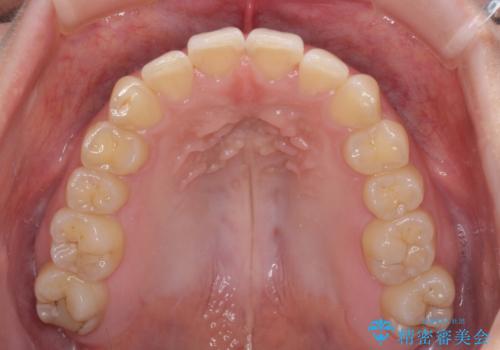

- 食いしばりが気になっていたとのことで来院された患者様です。

当初は睡眠時のマウスピースのみの製作をご希望でしたが、矯正治療の提案をしたところ、インビザラインにて矯正治療を行うこととなりました。

矯正治療中に食いしばりがより強くなることがあるため、半年に1回のペースでボツリヌストキシンによる咬合力緩和を並行して行うこととしました。

咬合力の緩和と食いしばりがちな咬み合わせが改善され、顎の負担が大幅に軽減されました。